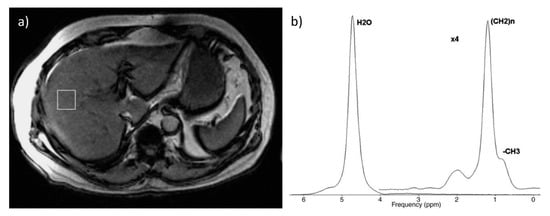

3. Magnetic Resonance Imaging Techniques